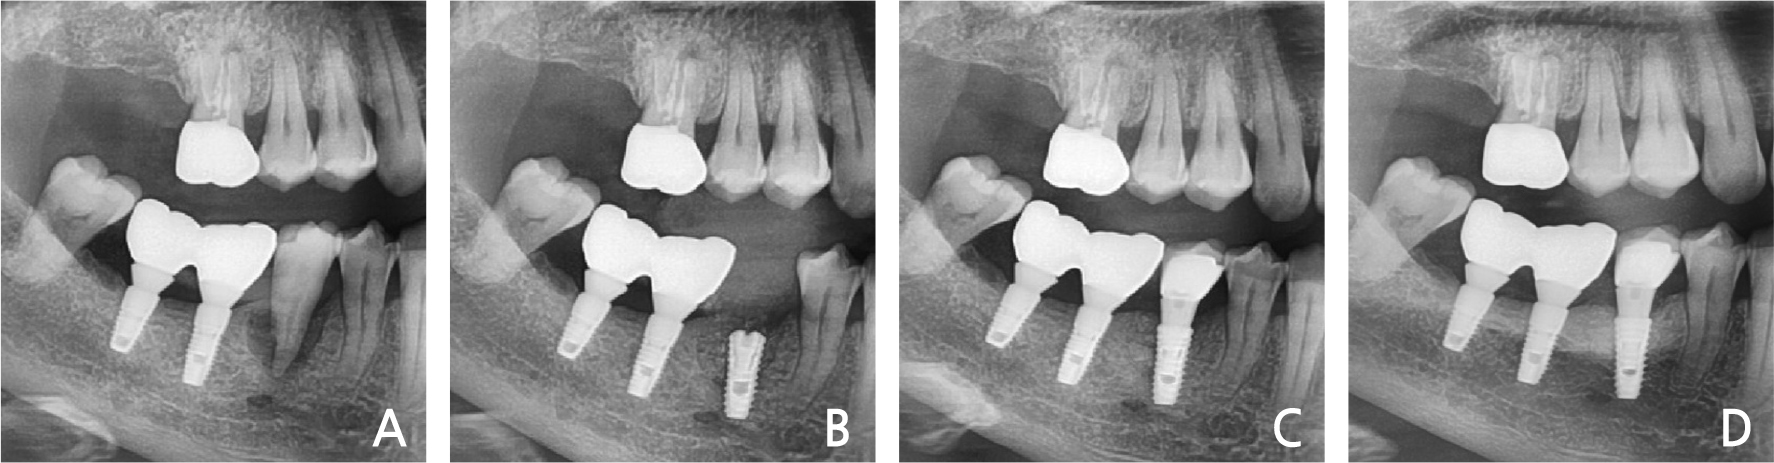

A 60-year-old man, a smoker, with no history of systemic disease visited the dental clinic complaining of severe pain in the right maxillary molars. Radiographic and clinical evaluations demonstrated severe bone loss and purulent exudates in the crevice area and bone loss in the proximal area of the right maxillary molars (Fig. 2A). Under local anesthesia, the right maxillary molars were extracted, and the infected tissue was completely removed. Immediate implant placement was performed with sinus elevation (Fig. 2B, 2C). The primary stability was attained by the inferior wall of the sinus and the remaining intact inter-septal bone. Restoration was performed after two months. After 3 years, no bone loss or preservation of the bony wall was observed (Fig. 2D).